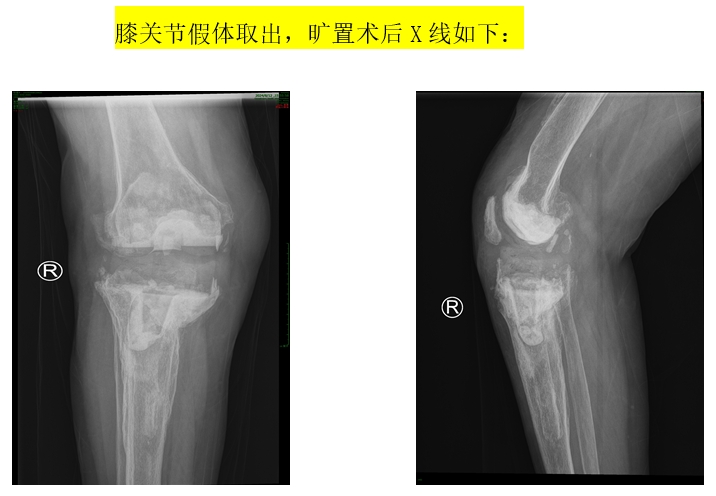

患者74岁女性,8年前在外院进行“右膝人工关节置换术”,6年前出现发热症状,右膝关节伤口部位有肿块,药物治疗后症状减轻但又多次复发,4个月前来到我院进行“右膝关节假体取出,清创,旷置术”,感染控制后进行“右膝人工关节翻修术”。患者入院后,谭红略主任组织专家针对此患者手术进行讨论,考虑患者经济情况较差,且胫骨内侧缺损较多,手术复杂、难度大,风险较高,一致认为目前常规的关节翻修假体已难以满足患者目前复杂的病情,需要寻找一种更加精准、个体化的治疗方案。在对患者病情进行深入分析后,手术团队决定采用个体化3D打印技术,制定个体化的关节翻修假体及相关手术方案。